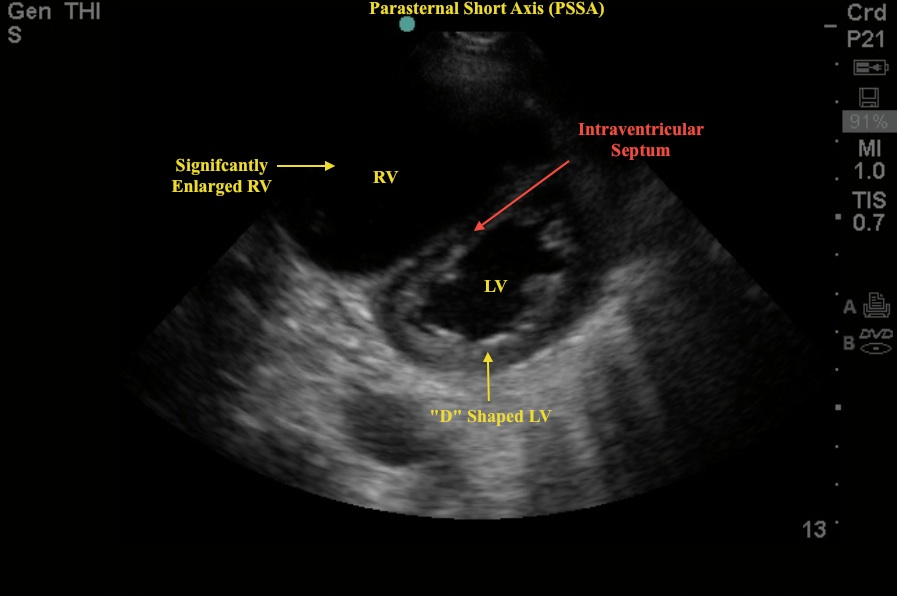

7/ TTE provides non-invasive assessment of right heart structure and function in PAH. Findings of the 3 Ss can guide differential diagnosis and assessment of PH severity.

1⃣Size – RV dilation/ RV shape

2⃣Squeeze – RV contraction

3⃣Smush – Interventricular septal flattening

9/ In PAH, it is the not pressure overload that causes septal flattening but instead it is the combination of high PVR and low compliance of the pulmonary vasculature.